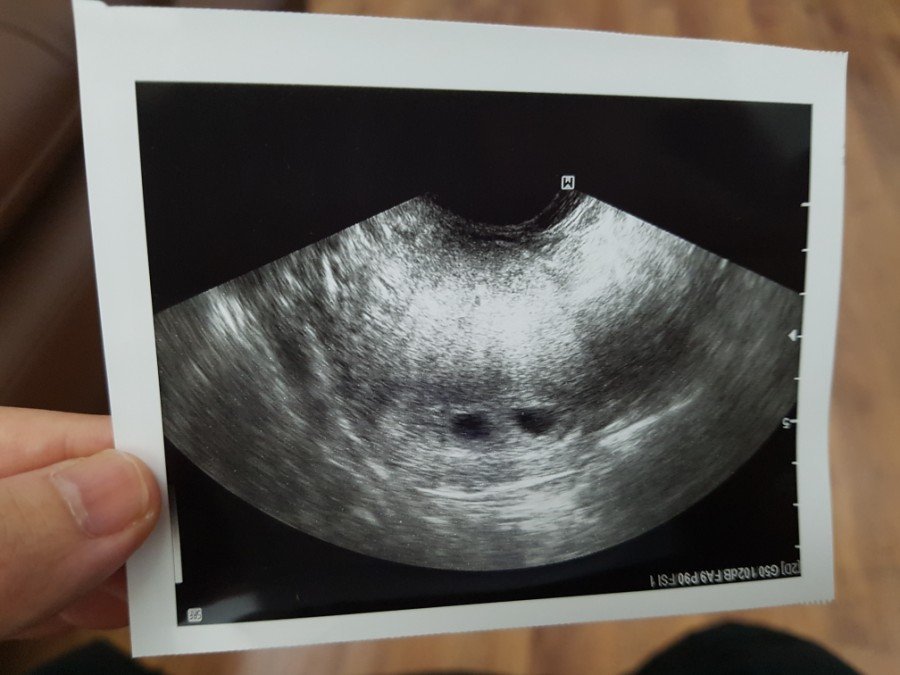

콧구멍시절

20180328_185824.jpg

예쁘게도 나란히 집을 지어놨더군 아.

자고로 '집'이란 기초가 튼튼해야 된단다.

집 지어놓은 것 보니

건축일 하는 엄마아빠 아가가 맞는구나.

"슈퍼 그뤠~~ 잇!"